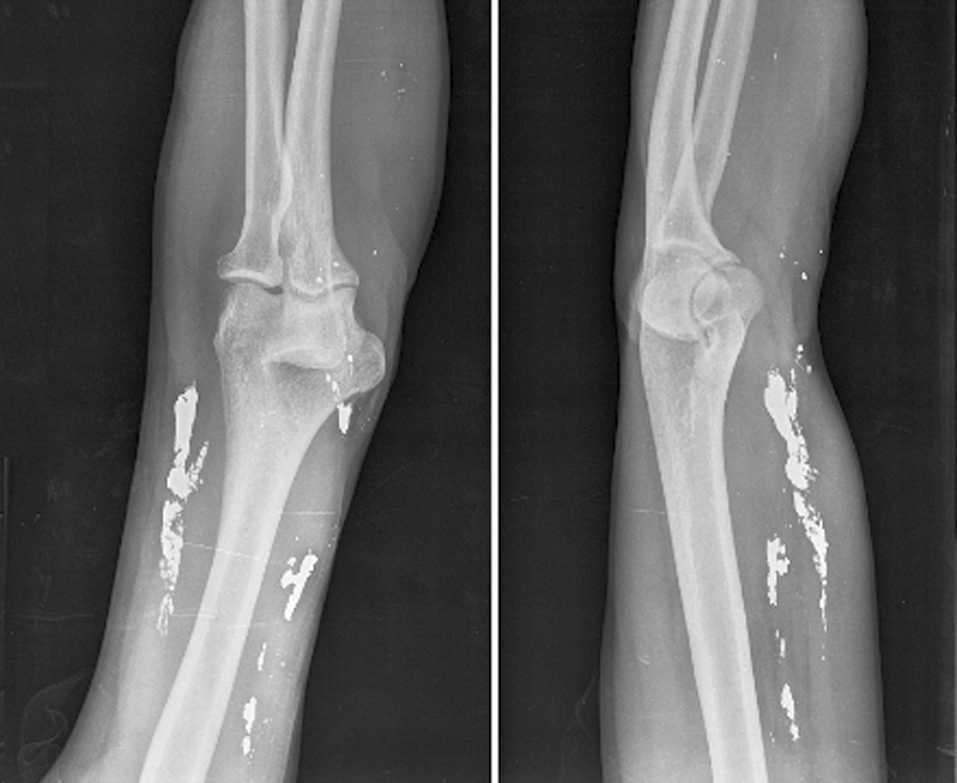

Los hallazgos de laboratorio no mostraron alteraciones destacables, con hemograma y hemostasia dentro de la normalidad. En la bioquímica sanguínea, los parámetros de función renal, hepática y electrólitos eran normales, y sólo destacaban los valores aumentados de lactatodeshidrogenasa (1.052 U/l) y creatincinasa (255,6 U/l). Los datos de la gasometría arterial (aire ambiente) fueron los siguientes: presión arterial de oxígeno de 82 mmHg, presión arterial de anhídrido carbónico de 38 mmHg, pH de 7,40 y SaO2 del 96,1%. La radiografía de tórax mostraba múltiples densidades metálicas de distinto tamaño, que se distribuían en ambos campos pulmonares, con áreas radiodensas que dibujaban en algunas zonas ramificaciones bronquiales (fig. 1). En la radiografía del brazo izquierdo se apreciaban numerosos depósitos metálicos en la fosa cubital, tejidos blandos y vasculatura (fig. 2). En la anamnesis dirigida, el paciente refirió haberse inyectado esa misma tarde 6 ml de mercurio en el antebrazo izquierdo con fines autolíticos.

Fig. 2. Radiografía lateral y anterior del brazo izquierdo, donde se aprecian agregaciones de mercurio en la fosa antecubital, tejidos blandos y vasos.